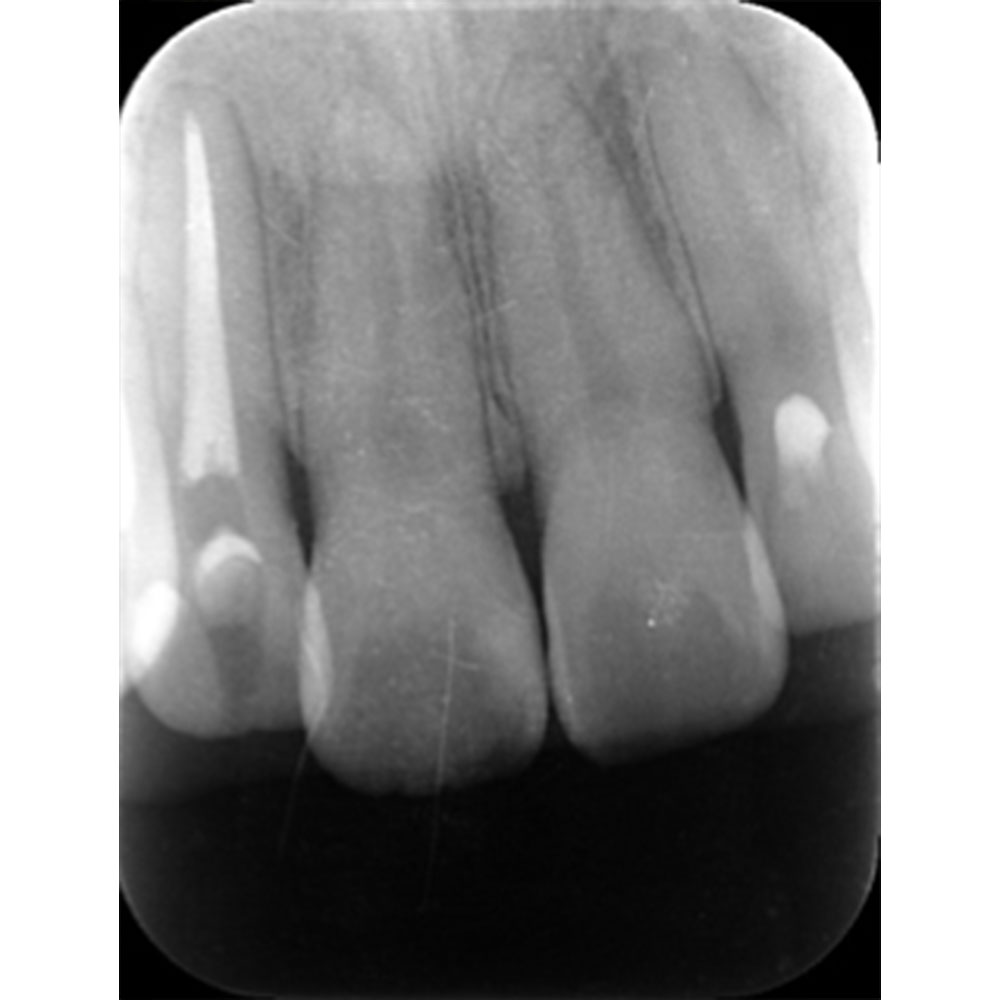

肉眼では根の先端は見ることができませんがマイクロスコープでは見ることができます。根の先端をこれ以上破壊しないように清掃して歯の神経があった場所にお薬を詰めることができました。根の治療後、かぶせ物までして半年たっても痛みがありません。

レントゲンを見ていただいて、歯の先までしっかり白いお薬が入っているのがわかります。